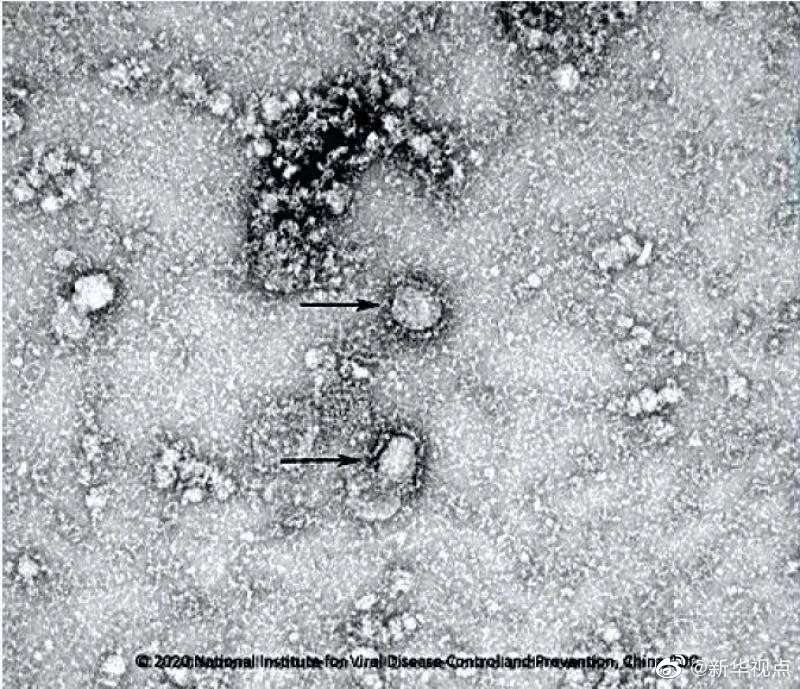

國家病原微生物資源庫于2020年1月24日發(fā)布了由中國疾病預(yù)防控制中心病毒病預(yù)防控制所成功分離的我國第一株病毒毒種信息及其電鏡照片、新型冠狀病毒核酸檢測引物和探針序列等國內(nèi)首次發(fā)布的重要權(quán)威信息,并提供共享服務(wù)。看病毒“真容”↓↓↓(記者田曉航、王秉陽)

好消息!中國疾控中心成功分離我國首株新型冠狀病毒毒種,它長這樣!-新華網(wǎng)